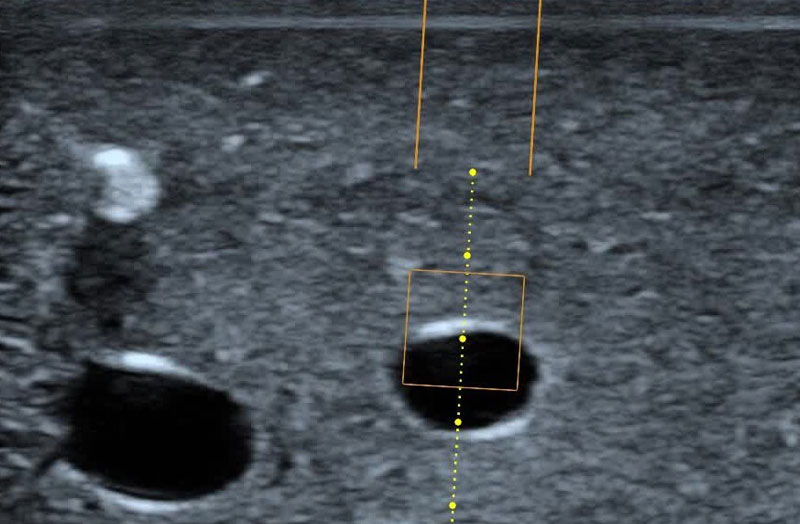

Needle Guidance